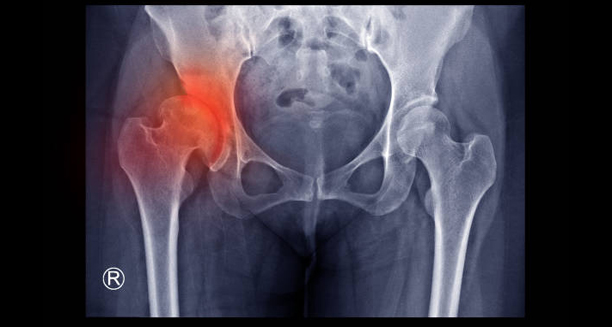

Developmental dysplasia of the hip (DDH) is a condition where the hip joint does not form properly in infants and young children. In this condition, the ball at the top of the thigh bone is not securely held in the socket of the pelvis. This can lead to instability, partial dislocation, or complete dislocation of the joint. Early detection and treatment are essential to avoid long-term mobility problems and joint degeneration.

The hip joint is a ball-and-socket structure. In babies with DDH, the socket may be too shallow, or the ligaments holding the joint in place may be too loose. This abnormal development can begin before birth or continue to evolve after the child is born. The condition ranges in severity from mild instability to full dislocation. Additionally, it can affect one or both hips, although the left hip is more commonly involved.